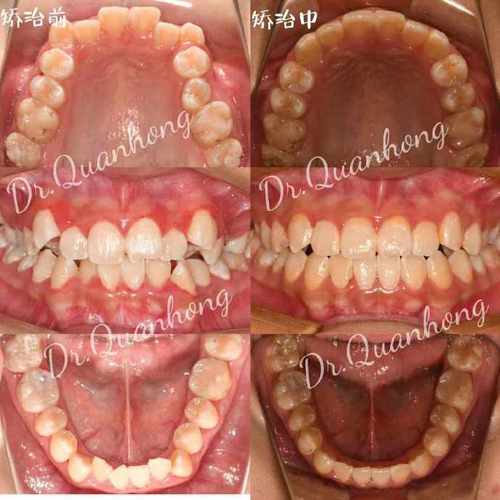

正畸拔牙是临床中常见的治疗手段,主要用于解决牙齿拥挤、前突、咬合关系异常等问题,而拔牙后的间隙管理是决定治疗效果的核心环节,间隙变化图作为记录和分析拔牙后牙齿移动轨迹、牙槽骨改建过程及最终效果的重要工具,通过动态影像和示意图直观展示了从间隙形成到关闭的全过程,为医生制定方案、监控治疗进度提供了科学依据,也让患者更清晰地理解治疗逻辑。

正畸拔牙通常选择第一前磨牙(上下颌各拔1-2颗),因其位置适中,既能提供足够间隙,又对邻牙功能影响较小,拔牙后,即刻形成的间隙大小约等于拔牙牙冠的近远中径(一般第一前磨牙牙冠宽度为5.5-7.0mm,平均约6.0mm),间隙两侧的牙齿(前牙和后牙)会因失去支撑而出现轻微倾斜:前牙可能向唇侧轻微移位,后牙向近中倾斜,但整体移动幅度较小(1mm),拔牙窝内充满血凝块,随后开始机化、骨改建,间隙变化图的初始阶段会清晰标注拔牙位置、间隙初始宽度,以及邻牙的初始倾斜角度,为后续移动设定基准。

主动间隙关闭阶段(3-12个月,核心阶段)

此阶段通过矫治器(如滑动法关闭曲、种植支抗等)施加持续、轻柔的生物力,推动牙齿快速移动,前牙(切牙、尖牙)整体向远中移动,后牙(磨牙)向近中移动,同时保持垂直高度稳定,间隙变化图特征显著:前牙切端逐渐向拔牙侧移动,后牙近中面与对颌牙建立初步接触,间隙宽度每月缩小约1.0-1.5mm;牙槽骨改建活跃,压力侧可见骨吸收透射影,张力侧骨密度增高;牙根位置随牙齿移动调整,逐渐趋于平行。

精细调整阶段(12-18个月)

当间隙基本关闭后,进入细节优化阶段,医生通过调整弓丝转矩、更换细丝(如0.018英寸不锈钢丝)进行“轻力细调”,纠正牙齿的轻微扭转、转矩异常,建立稳定的咬合关系(如尖牙引导、组牙功能颌),间隙变化图显示:牙齿排列整齐,牙根平行,牙槽骨改建完成,密度均匀;牙龈形态逐渐恢复,若存在牙龈凹陷,可能需通过牙周手术或正畸牵引改善。